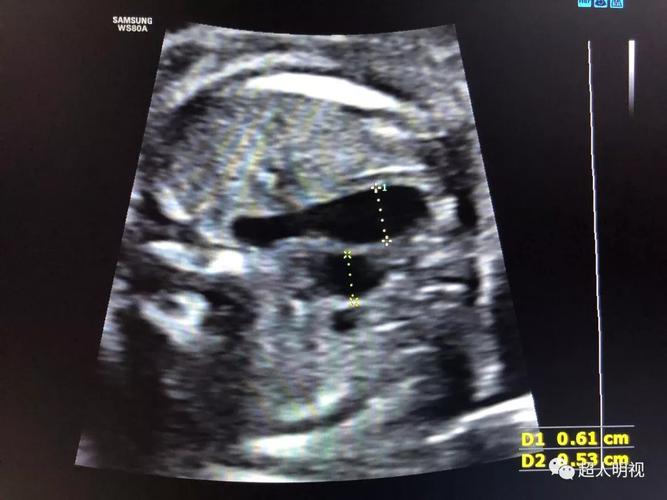

胎儿三血管气管切面

胎儿三血管气管切面,胎儿静脉导管解剖

异常篇:三血管气管切面——胎儿心超最重要的切面

正常篇:三血管气管切面——胎儿心超最重要的切面

充分理解胎儿三血管气管切面(正常篇)

胎儿双顶径切面图解